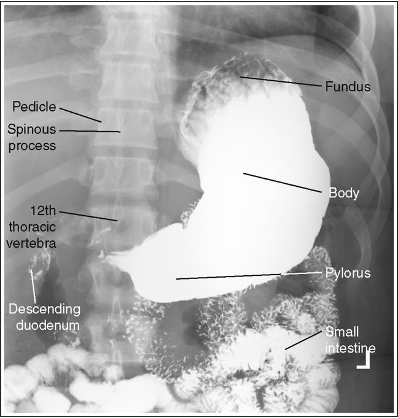

What position is this patient in?

AP (Supine, barium in fundus and spine is straight)